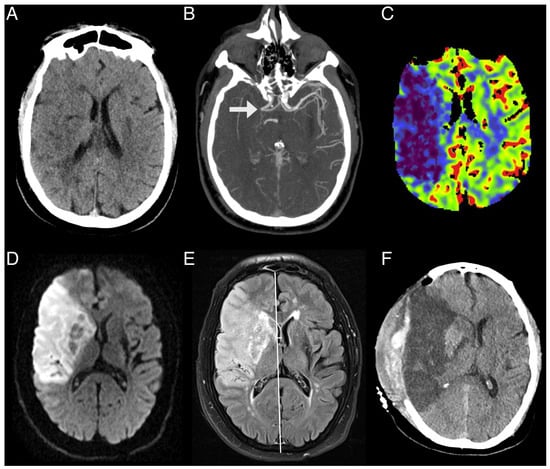

- Admission multimodal CT protocol, including non-contrast CT (NCCT), CT angiography (CTA), and CTP.

- Neuroimaging evidence indicating significant cerebral edema, exemplified by a midline shift ≥6 mm or an infarct encompassing over half of the MCA territory.